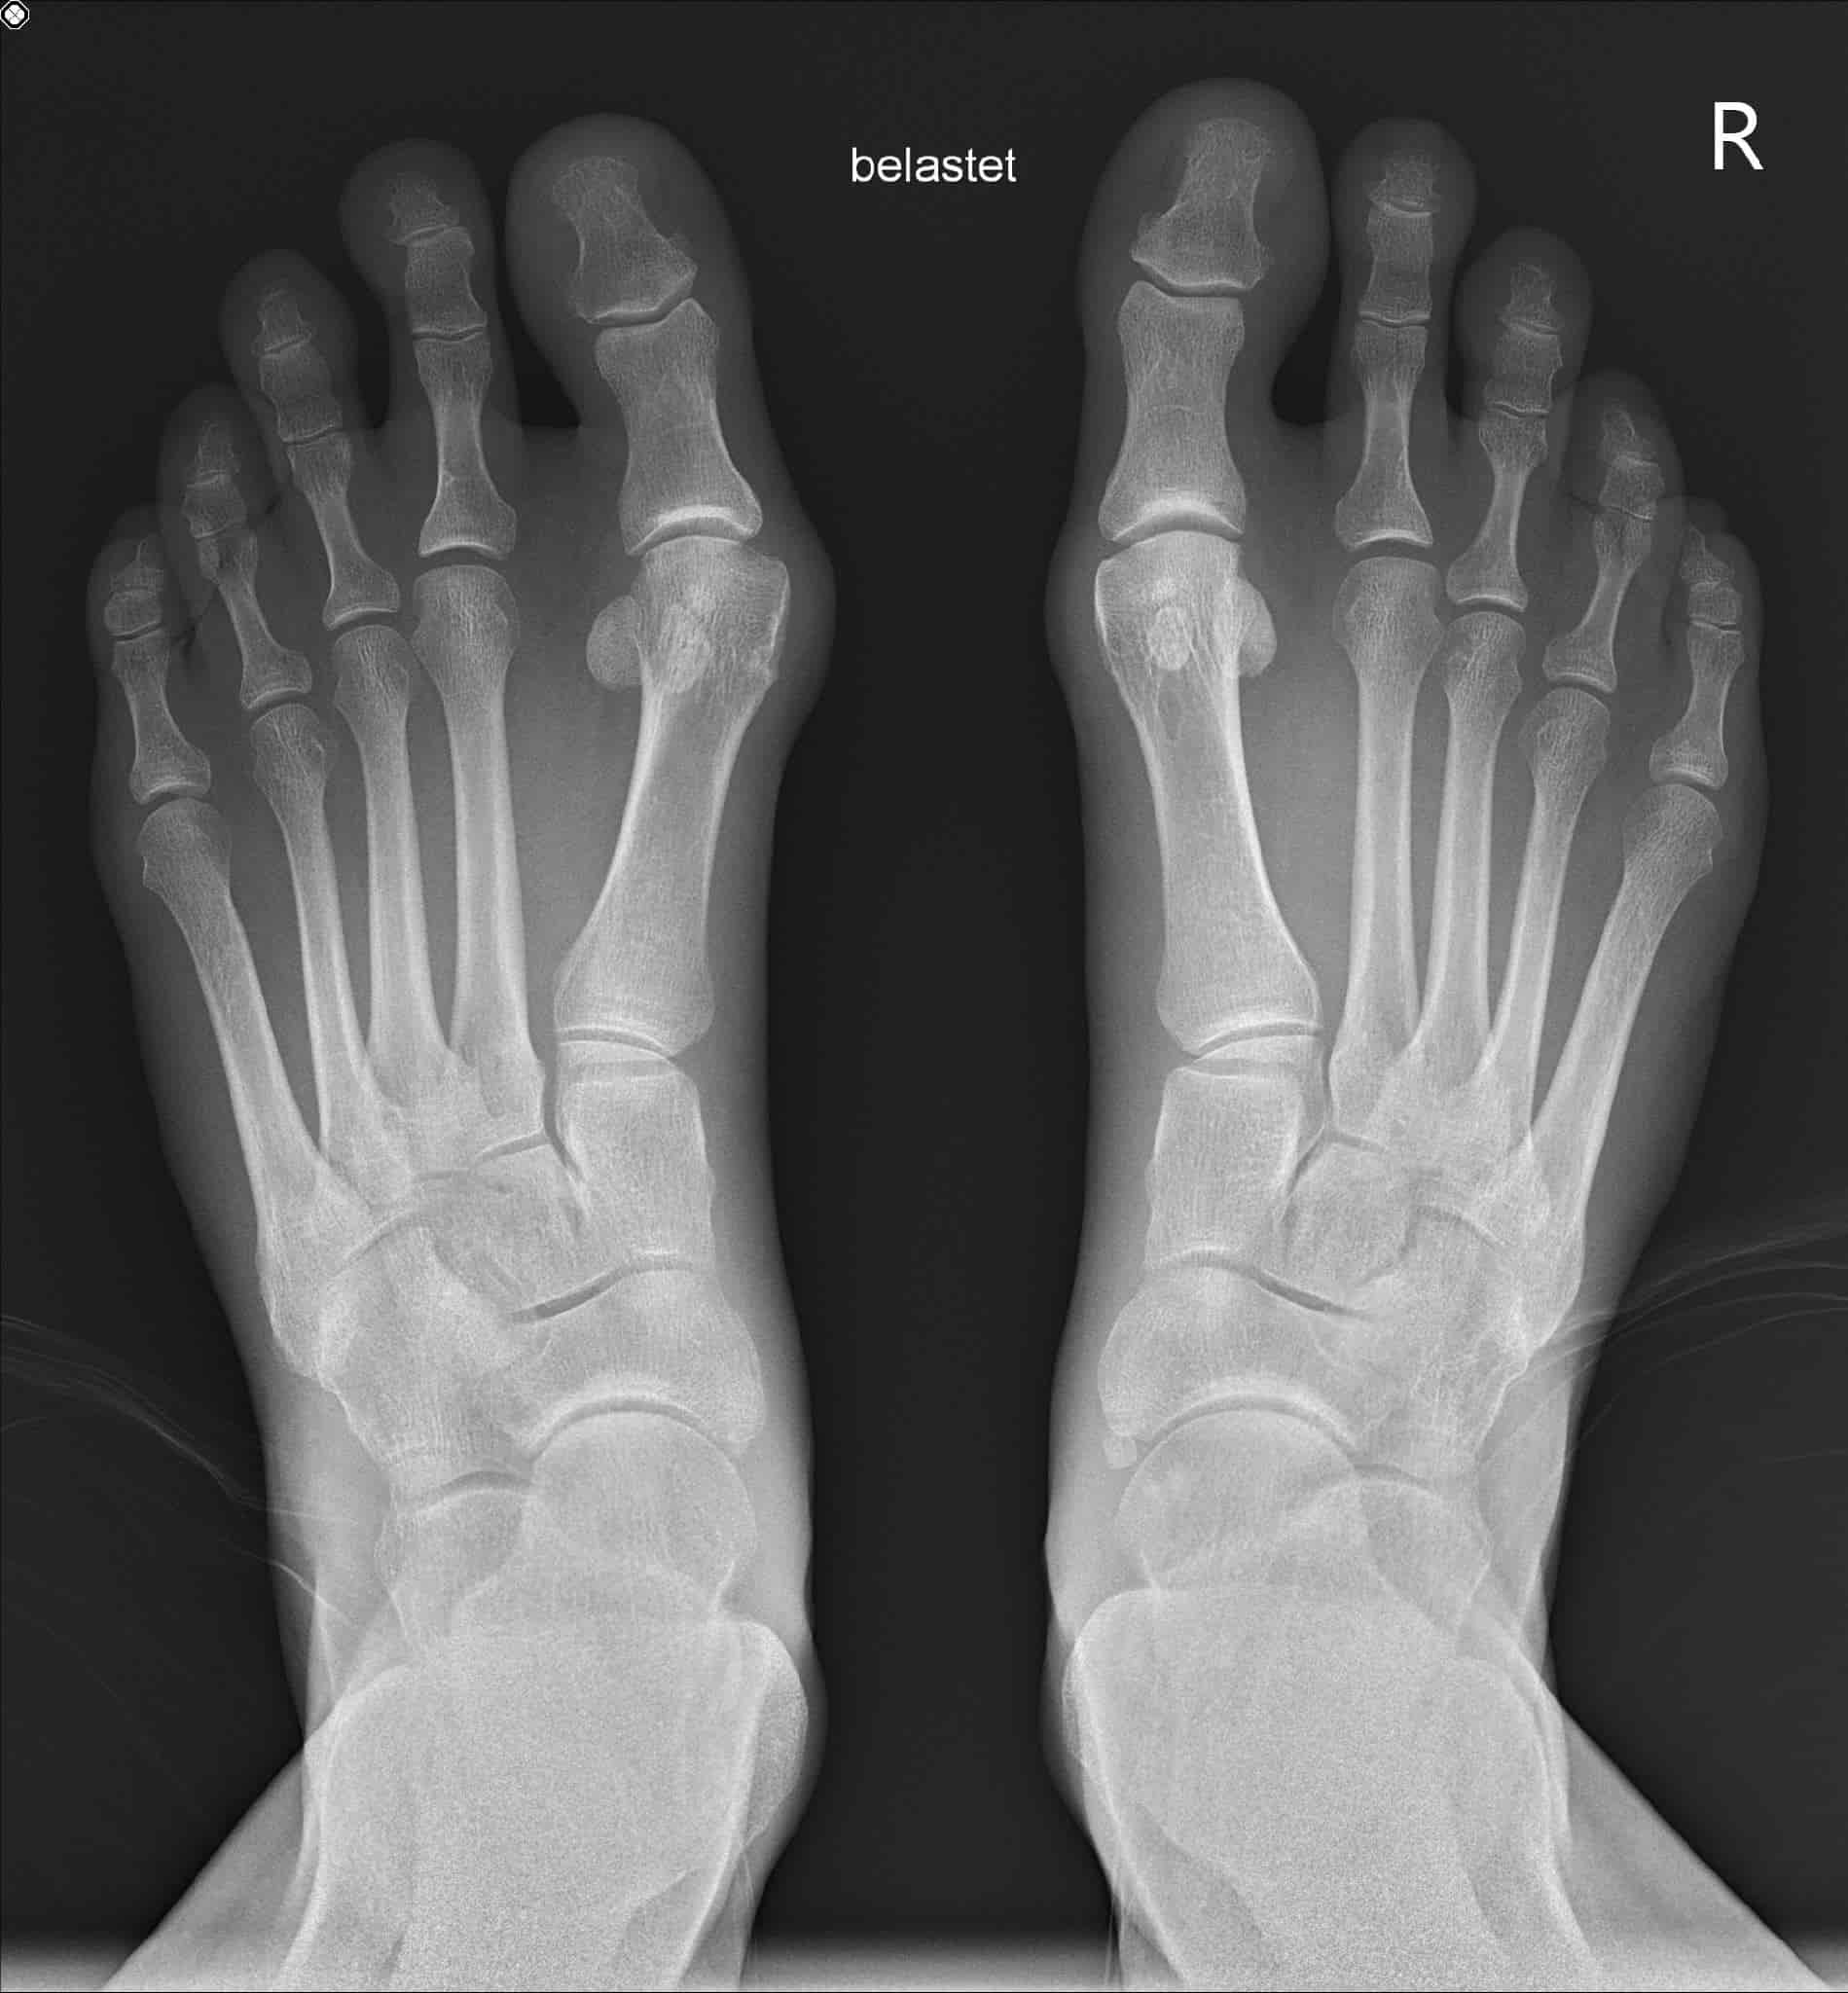

My information session takes place in May, during which I learn a lot about hallux, its causes and treatment options. The X-ray images speak for themselves, and all the risks and opportunities are laid openly on the table. Without any time pressure, I take the information home with me and think about it in detail. The operation, which initially seemed like a spectre, becomes a real option.

The idea of having not only the left foot - with the advanced hallux valgus - but also the right hallux valgus corrected at the same time shocked me at first. But the longer I think about it and the more I find out about the procedure, the clearer I realise the advantages: just one operation, just one rehabilitation process and the hallux valgus chapter could be closed in one fell swoop.